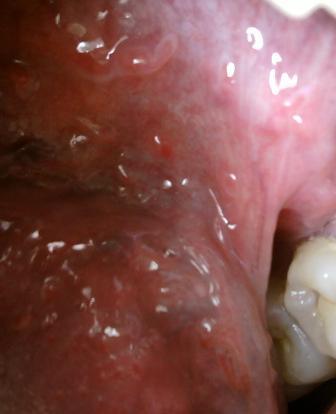

石家庄九州皮肤病医院 > 尖锐湿疣 > > > 尖锐湿疣治疗须知尖锐湿疣性病是相当顽固,因此建议大家一定要及时诊治,以免耽误诊治,加重病情,加大治疗的难度。因此患病之后对于疾病应该有一个豁达的心态和一个积极的心态,相信医学,坚持诊治,才能更好的治愈疾病。

尖锐湿疣治疗须知要想早日治愈疾病,就应该根据自身病情制定适合的治疗方法,对症诊治,相信经正规权威的诊治是可以达到比较好的治疗效果的。对于尖锐湿疣这种顽疾,专家还是建议最好是采取综合的治疗方法,与此同时,必要的护理工作也是不能少的。积极配合主治医师诊治,保持一颗愉快的心态,才能更快的治愈疾病。